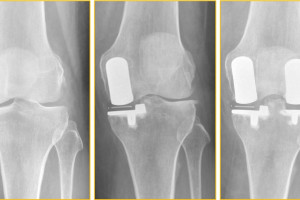

Behandlung einer Knie-Arthrose mit 2 Schlittenporothesen

Wir zeigen die Bilder einer Patientin, bei der sich nach der erfolgreichen Behandlung einer innenseitigen Knie-Arthrose mittels innenseitiger Schlittenprothese Schmerzen und Verschleißzeichen auf der Knie-Außenseite entwickelt haben. Die Behandlung ...